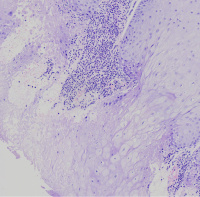

外阴多发赘生物,请教老师们,怎么报告?

性别

女

年龄

62

发现外阴数十粒丘疹样结节,伴溃疡

外阴丘疹样赘生物

灰白色组织两粒0.5*0.3cm

考虑:疱疹病毒感染

疱疹性皮炎。

符合疱疹性皮炎。